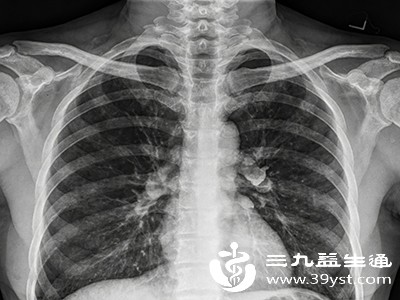

胸膜炎是一种常见的胸部疾病,当致病因素刺激胸膜引发炎症时,患者会出现胸痛、咳嗽、呼吸困难等不适症状,严重影响生活质量。面对胸膜炎,科学合理的治疗至关重要。其治疗方法并非单一模式,而是需要根据病因、病情严重程度等因素,综合运用药物治疗、手术干预以及生活调理等多种手段,才能有效控制病情,促进身体康复。